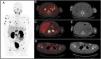

Radiotherapy is a treatment with curative intent, both in patients with primary diagnosis of prostate cancer (PCa) and in patients presenting with biochemical recurrence after radical prostatectomy (RP). Moreover, the use of stereotactic body radiotherapy as a metastasis directed therapy in patients with oligometastatic PCa has significantly increased in the recent years. Conventional imaging techniques, including transrectal ultrasound, computed tomography (CT), morphologic magnetic resonance and bone scintigraphy have traditionally played a minor role in all those clinical scenarios due to its low diagnostic accuracy. The recent development of the positron emission tomography (PET) radiotracer 68Ga-PSMA binding to the prostate specific membrane antigen (PSMA), a transmembrane glycoprotein overexpressed in PCa cells, has shown promising results. Detection rates for PCa lesions are higher than CT and higher than the best technique available, the PET/CT with choline. Its superiority has been demonstrated even at very low PSA levels (<1 ng/ml). This increase in diagnostic accuracy represents a potential impact on patient management, especially in radiotherapy. Even if this imaging technique is already available for routine clinical practice in some European countries, in Spain, unfortunately, there is very limited access. In this review, we analyze the main studies that investigate the usefulness of 68Ga-PSMA PET/CT in patients with PCa and its potential impact on radiotherapy treatments. In addition, we compared the 68Ga-PSMA PET/CT, with the multiparametric magnetic resonance imaging and the PET/CT with choline, in the different clinical scenarios.